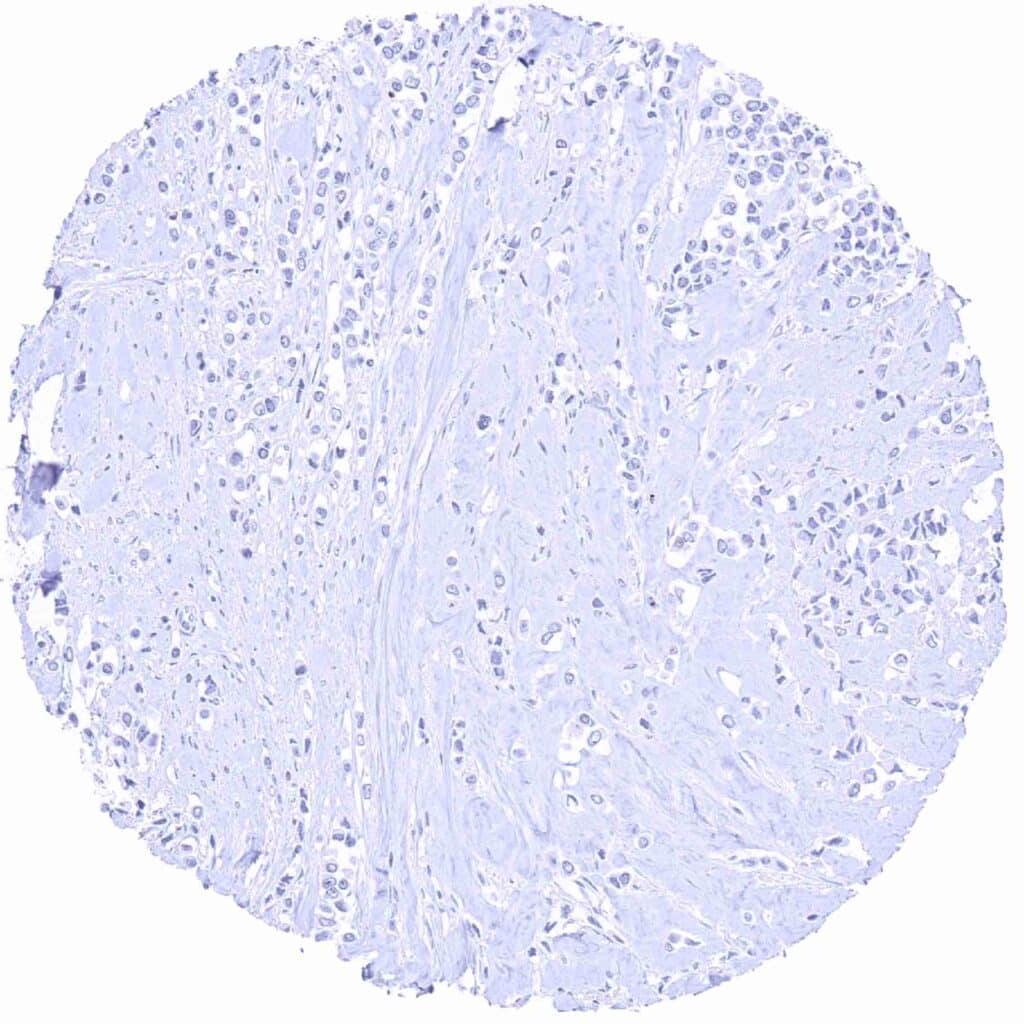

Breast – Prostein negative invasive lobular breast cancer